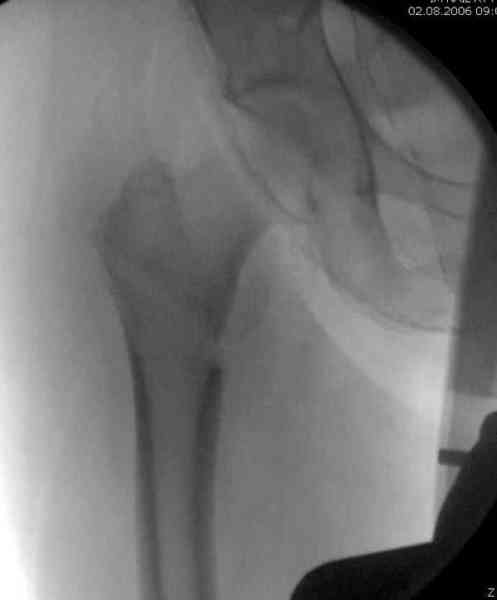

В общем, сделали. См. приложение.

Длина и из-за этого ось получились не совсем такие, как хотелось бы, все-таки срок после той операции уже 6 недель. Может быть, стоило провести дистракцию аппаратом неделю-другую. Заранее спасибо за комментарии и критику.

Наверное так и надо сделать. Будет непросто предотвратить при введении смещение Гаммы кнаружи через имеющийся дефект кортикала. Уверен, Александр Николоевич, Вы с эти справитесь. Удачи!

Александр, поздравляю от души, отличная работа, вообще-то и у меня тоже были опасения по поводу латеральной стенки. Идеальное показаниt к применению импланта закрытым методом при таких переломах, когда болт замыкается в штифте, конструкции придается угловая жесткость, примерно как в Blade Plate.

При отсутствии таких конструкций, другим альтернативным методом фиксации можно было рекомендовать короткий DHS с двумя шурупами открытым методом, а в диафиз ретроградний штифт.